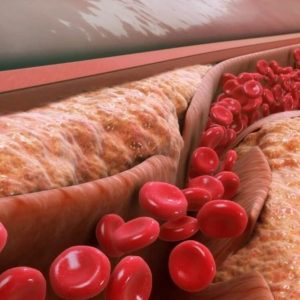

پکیج چربی خون